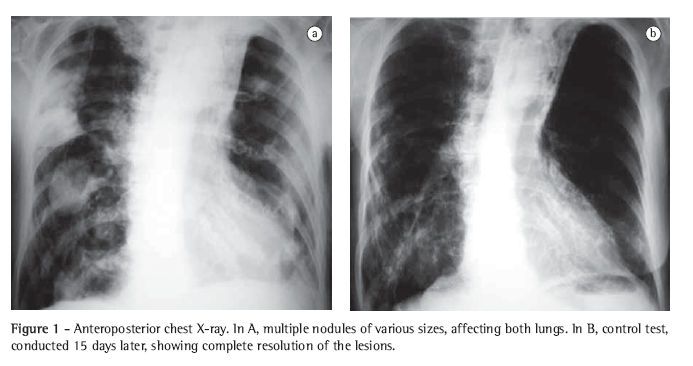

Case reportAn 89-year-old white woman presented with COPD and bronchiectasis in the upper left lobe for 20 years. A functional diagnosis of COPD was made by calculating the ratio of the forced expiratory volume in one second/forced vital capacity, which was 41.2% after the use of bronchodilator in the pulmonary function test. She had been on daily use of tiotropium bromide, long-acting anticholinergics, associated with inhaled corticosteroid since September 2004; in acute exacerbations, she used systemic corticoids associated with broad spectrum antibiotics. She had presented cough with purulent sputum, 38°C fever, night sweats, severe prostration, dyspnea and anorexia for 5 days. A 10-day course of ciprofloxacin was prescribed, a treatment that resulted in no clinical improvement, and the patient was hospitalized for 10 days due to worsening of the clinical status. In this first admission, the chest X-ray showed thickening of the bronchial walls, small, ill-defined opacities in the right upper and lower lobes, as well as atelectasis with bronchiectasis in the left upper lobe. Klebsiella pneumoniae was isolated through sputum culture. Ceftriaxone, piperacillin and tazobactam were prescribed. The patient was discharged after improvement of the fever and cough. After discharge, there was recurrence of the symptoms, with worsening of the dyspnea. A chest X-ray was performed in the home, using a portable device. The X-ray showed disseminated nodules in the lungs, prompting a second hospitalization (Figure 1). Upon examination, the patient presented a general aspect of suffering: prostration; paleness; tachypnea (44 breaths/min); tachycardia (120 bpm); axillary temperature, 37°C; arterial pressure, 120/80 mmHg; peripheral oxygen saturation, 84% in room air. There were rhonchi in both lungs. The rest of the examination evidenced no alterations. Laboratory test results were as follows: 3,260,000 erythocytes/mm3; hematocrit, 28%; hemoglobin, 9.6 g/dL; 11,130 leukocytes/mm3; rods, 5%; segmented, 64%; eosinophils, 0%; lymphocytes, 10%; pH, 7.4; arterial oxygen tension, 68.7 mmHg; arterial carbon dioxide tension, 42.8 mmHg; peripheral oxygen saturation, 93%-with oxygen at 3 L/min using a nasal catheter; urea, 44.3 mg/dL; creatinine, 1.26 mg/dL; sodium, 135 mEq/L; and potassium, 5.4 mEq/L. The results of the liver function test, coagulation profile, echocardiogram and pelvic ultrasound were normal. Blood culture and serology were negative for HIV.

Initially, the association trimethoprim-sulfamethoxazole was prescribed, without clinical response. A 15-day course of amikacin, with imipenem and cilastatin, was then prescribed, resulting in an excellent clinical and radiological response (Figure 1). The patient was discharged with a prescription for an additional 8 weeks of trimethoprim-sulfamethoxazole.

The chest X-ray presentation of pulmonary nocardiosis is nonspecific. The most common radiological findings are consolidations and large irregular nodules. Nodules, cavitated masses, pleural effusion, pneumothorax, ground-glass opacities and interstitial patterns can occur as well.(1,4,5,11) Some studies show that, in HIV-infected patients, there is a higher percentage of cavitated lesions.(8) Alveolar consolidation in the upper lobes is often confused with pulmonary tuberculosis.(6) Although the alterations observed on CT scans are similar to those of the conventional X-rays, CT is superior in demonstrating the exact location and extent of the lesions, as well as in the differentiation between pulmonary and pleural lesions.(5) In the case reported, the patient presented nodules of various sizes, disseminated throughout both lungs, and some of those nodules were cavitated.